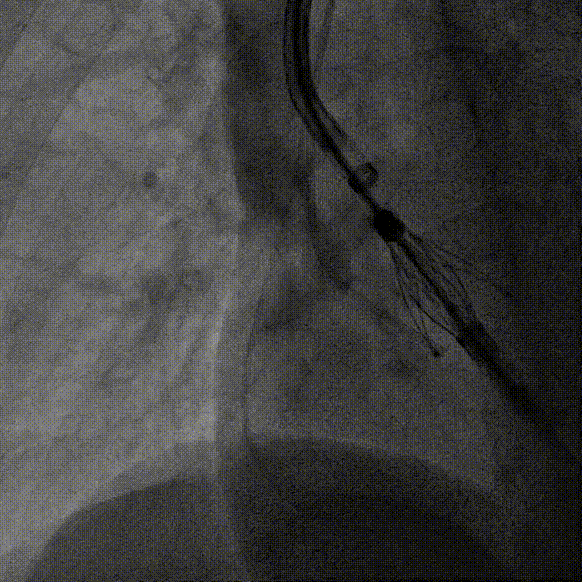

左冠造影

小右冠,弥漫性病变

LAD术后造影

根部造影

长鞘植入

输送器定位

右窦中心对齐

定位键窦对齐

无窦确认

右窦观察

左窦确认

深度确认

一键脱钩

术后造影